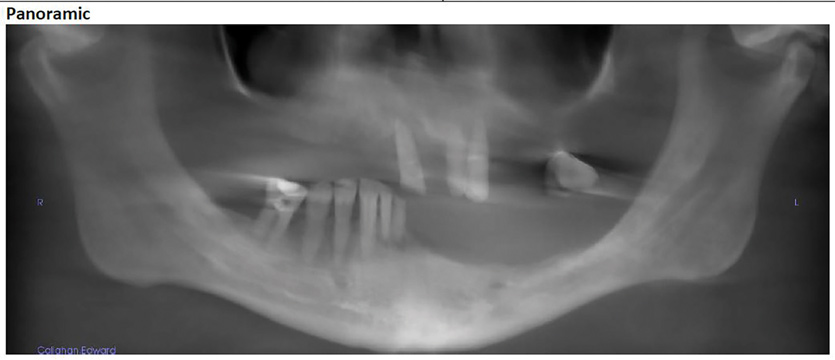

Figure 26: The patient’s final panoramic radiograph shows all surgical placement.

Figure 26